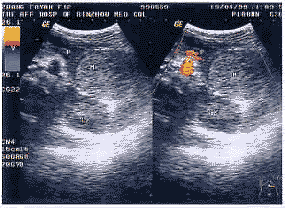

患者,女,12岁,因持续性腹痛2 d入院,查体:心肺正常,腹部平坦,腹肌紧张,全腹压痛,以左上腹为主,肝脾肋下(-),腹水(-)。超声检查:肝、胆、脾、双肾未见异常,胰头体部未见异常,胰尾显示不满意,于左上腹胰尾区,脊柱左侧、脾脏与左肾上极之间测及8 cm×6 cm×7 cm大小中等回声团块,部分边界清晰,内部回声较均匀,后方回声稍有增强效应。团块周围见肠道回声,腹盆腔内见少量无回声区。彩色多普勒血流显像(CDFI)示:团块内未见血流信号,周边可见血流信号,Vmax 44 cm/s,RI 0.54(图1)。超声诊断:①左上腹实质占位性病变,提示胰尾区肿瘤;②腹盆腔少量积液。CT检查显示:左上腹、左肾、脾和胃后壁之间有一密度较均匀的实质性占位性病变,大小为8 cm×6 cm×7 cm。手术中发现肿物为囊性,与大网膜、脾下极、结肠脾区紧密粘连,肿物大小为10 cm×10 cm×6 cm,壁厚,表面附少许胰腺组织,位于胰体尾之间,切开团块内为陈旧性血液及凝血块,诊断为胰尾囊肿内血管破裂出血,血块机化。病理诊断:腹腔囊肿,内为渗出物及炎性坏死组织,部分区域有机化。

图1 胰腺囊肿内血管破裂(P-胰腺,M-肿块,LK-左肾)